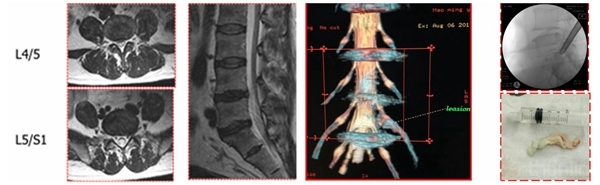

3D-MRI:普通MRI无异常,3D-MRI发现游离髓核,行脊柱内镜取出游离髓核

3D-MRI:对一些特殊类型的椎间盘突出(如极外侧腰椎间盘突出)可起到更加准确的诊断作用

有些病例椎板间入路手术更加简单,尤其对于L5/S1脱垂病例

L5/S1钙化型突出(骺环离断症),椎板间减压更加充分彻底,需配备磨钻动力系统